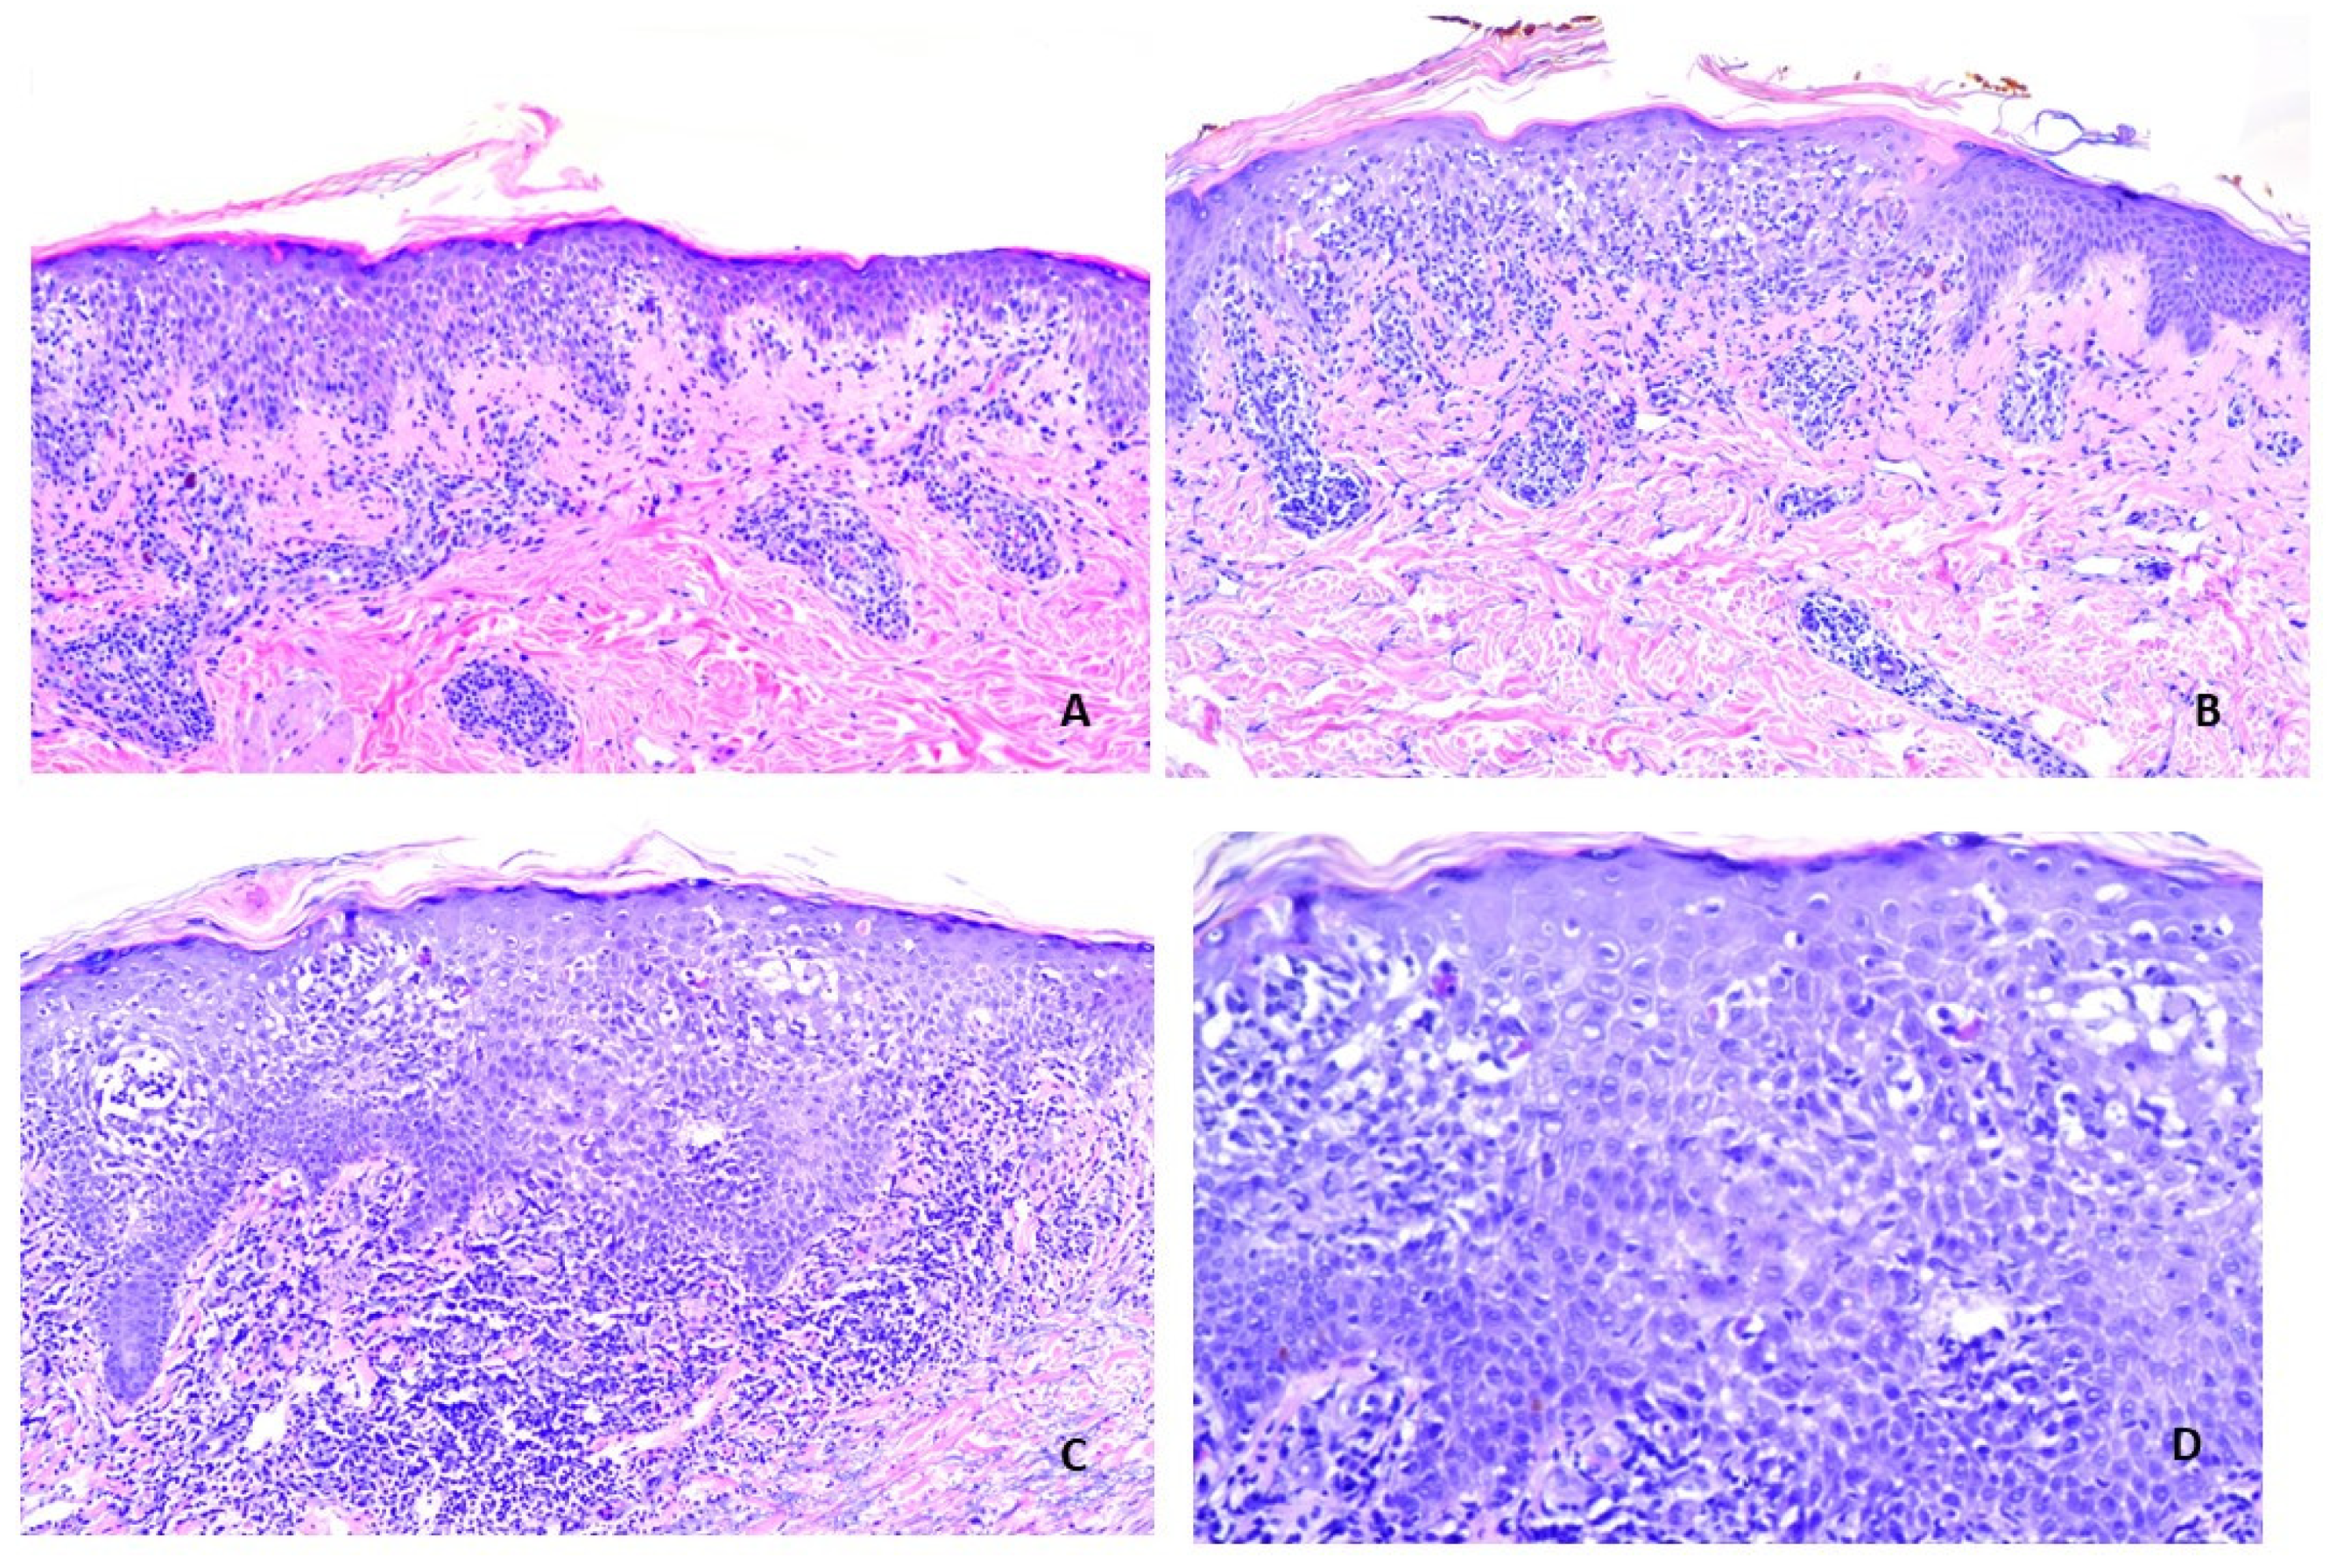

| Histopathologic | |||

| Lichenoid Interface Dermatitis | Present | Present | Present |

| Compact Orthokeratosis | Characteristic | May be present | May be present |

| Wedge-shaped Hypergranulosis | Characteristic | May be present | May be present |

| Focal Parakeratosis | Not characteristic | May be present | May be present |

| Focal Interruption of Granular Layer | Not characteristic | May be present | May be present |

| Sawtoothing of Rete Ridges | Characteristic | May be present | May be present |

| Focal Spongiosis | Not characteristic | May be present | May be present |

| Necrotic Keratinocytes Number At All Levels of Epidermis | Fewer than LDE, V-ILE Not characteristic. | Larger number [93]. May cluster. May be seen at all levels. | May be more than seen in ILP. This feature was seen in 5/15 (33%) cases reported herein. |

| Location of Cytoid Bodies in Epidermis | Lower spinous layer | Lower spinous layer; may also be seen in upper spinous, granular, cornified layers. | Lower spinous layer; may also be seen in upper spinous, granular, cornified layers. |

| Lymphocytic Infiltrate Throughout Epidermis | Not characteristic | May be present | Present in 6/15 (40%) cases in series reported herein. |

| Location of Lymphocytic Infiltrate in Dermis | Superficial (papillary) | Superficial and may extend deeper | Superficial and may extend deeper |

| Deep Perivascular Infiltrate | Rarely seen | May be present | Often present in lichen striatus Occasionally seen in other lichenoid reactions |

| Focally lichenoid or patchy infiltrate | Dense band-like infiltrate is characteristic. | May be present | Present in 7/15 (47%) of cases reported herein. |

| Perieccrine or Periadnexal Infiltrate | Not characteristic. May be seen in adnexotrophic variants. | Uncommon | Often seen in vaccine-induced LS. |

| Eosinophils in Infiltrate | Not characteristic | May be present. Found in 2/15 cases (13.4%) in study directly comparing LDE to ILP [93]. | May be present. Found in 1/15 (6.7%) cases reported herein. |

| Plasma Cells in Infiltrate | Not characteristic | May be present | May be present |

| Granuloma Formation | Not characteristic | May rarely be present | Seen in 1/15 cases in series reported herein. |